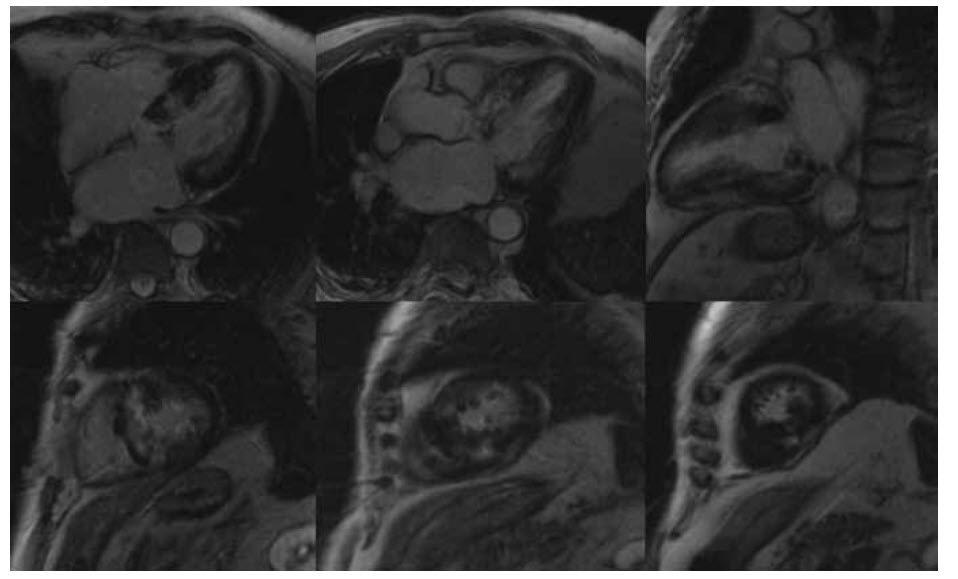

Video below shows the perfusion images (stress, top row; rest, bottom row).

The late myocardial enhancement is shown below in the four-chamber view (top left), three-chamber view (top right), and two-chamber view (bottom).

Which one of the following statements is correct?

A. There is myocardial infarction of the Cx territory

B. There is an inducible perfusion defect in the Cx territory

C. There is an inducible perfusion defect in the RCA territory

D. There is an inducible perfusion defect in the LAD and Cx territory

E. There is an inducible perfusion defect in the LAD territory